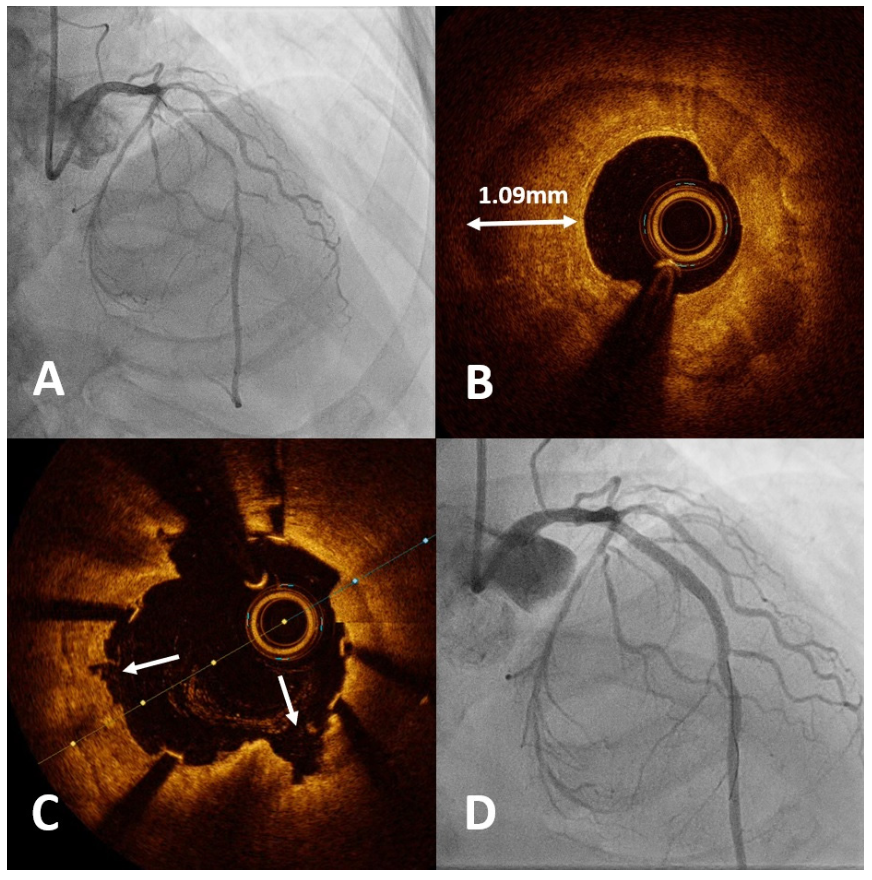

Rotatripsy patient #7. A 68-year-old man with hypertension, type 2 diabetes mellitus, and dyslipidemia underwent elective PCI for progressive angina. He was found to have severely calcified diffuse disease in the proximal to mid LAD (Figure 1A). The OCT catheter was unable to pass the lesion for baseline assessment, therefore, upfront RA was performed with a 1.5-mm burr at 180,000 rpm. Several runs were performed successfully and baseline OCT was then acquired, showing concentric 360° calcification, with a maximum calcium thickness of 1.09 mm (Figure 1B). Although RA allowed enough lumen gain to pass the OCT catheter, the imaging showed minimal modification to the thick concentric calcification. Predilation with a 2.75 x 15-mm non-compliant balloon did not open well, therefore, a 2.5 x 12-mm IVL balloon was used to deliver 80 pulses of lithotripsy. Following stenting and balloon postdilation, final OCT showed good stent expansion with deep calcium cracks created by the lithotripsy (Figure 1C). Final angiographic result is shown in Figure 1D.

Rotatripsy patient #10. A 76-year-old man with hypertension and end-stage kidney disease underwent staged PCI to his calcified RCA following an anterior ST-segment-elevation MI (Figure 2A). After small balloons were unable to pass the mid RCA to predilate the distal vessel, the workhorse guidewire was exchanged for a RotaWire Floppy (Boston Scientific), with multiple runs using a 1.5-mm burr at 180,000-200,000 rpm across the mid RCA. The lesion was further predilated with a 2.0 x 15-mm non-compliant balloon to facilitate IVUS assessment. This showed concentric 360° calcification in the mid RCA with a minimal lumen area (MLA) of 3.5 mm2 (Figure 2B) and a calcified nodule in the proximal RCA (Figure 2C). A 3.0 x 12-mm IVL balloon was used to deliver 50 pulses of lithotripsy, followed by further predilation with a 3.0 x 15-mm non-compliant balloon. Final IVUS following stenting and balloon optimization showed a minimal stent area (MSA) of 6.7 mm2, with a stent expansion of 94% (Figures 2D and 2E). Final angiographic result is shown in Figure 2F.